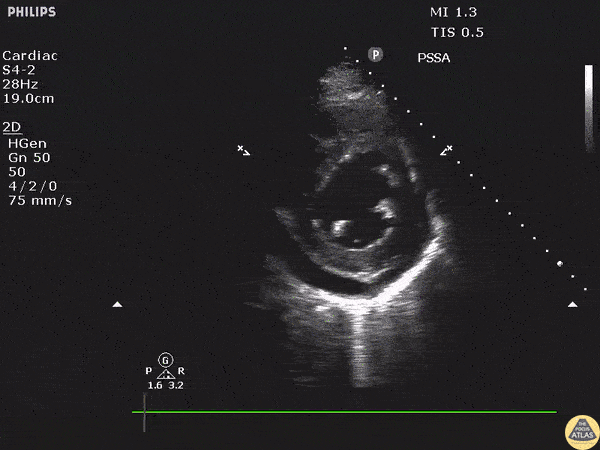

Parasternal short axis view of a pericardial effusion. View the thread at the link below for parasternal long axis and associated EKG findings. Image courtesy of Robert Jones DO, FACEP @RJonesSonoEM Director, Emergency Ultrasound; MetroHealth Medical Center; Professor, Case Western Reserve Medical School, Cleveland, OH View his original post here